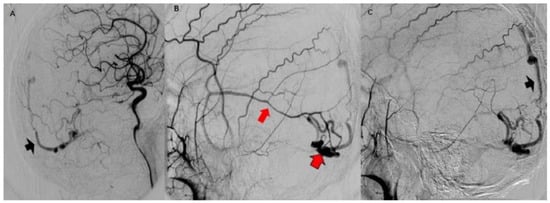

3.2. Imaging Studies